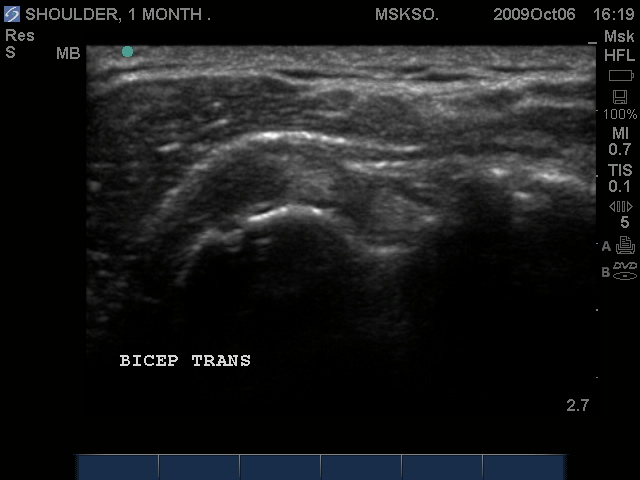

Supraspinatus tendon transverse over humeral head articular surface (articular surface changes in echotexture to hypoechoic)

"Cartilage Interface Sign" the hyperechoic rim over the hypoechoic articular cartilage is not usually seen unless a fluid layer is between the tendon and cartilage surface. When the tendon is resting normally over cartilage the interface is only hypoechoic.